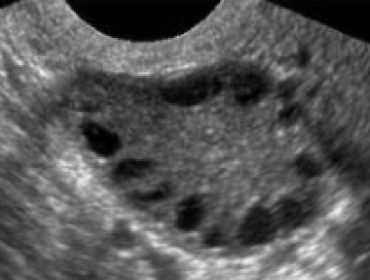

In this episode we trace the history of polycystic ovarian syndrome, learn about the underlying physiology, and how to diagnosis it.